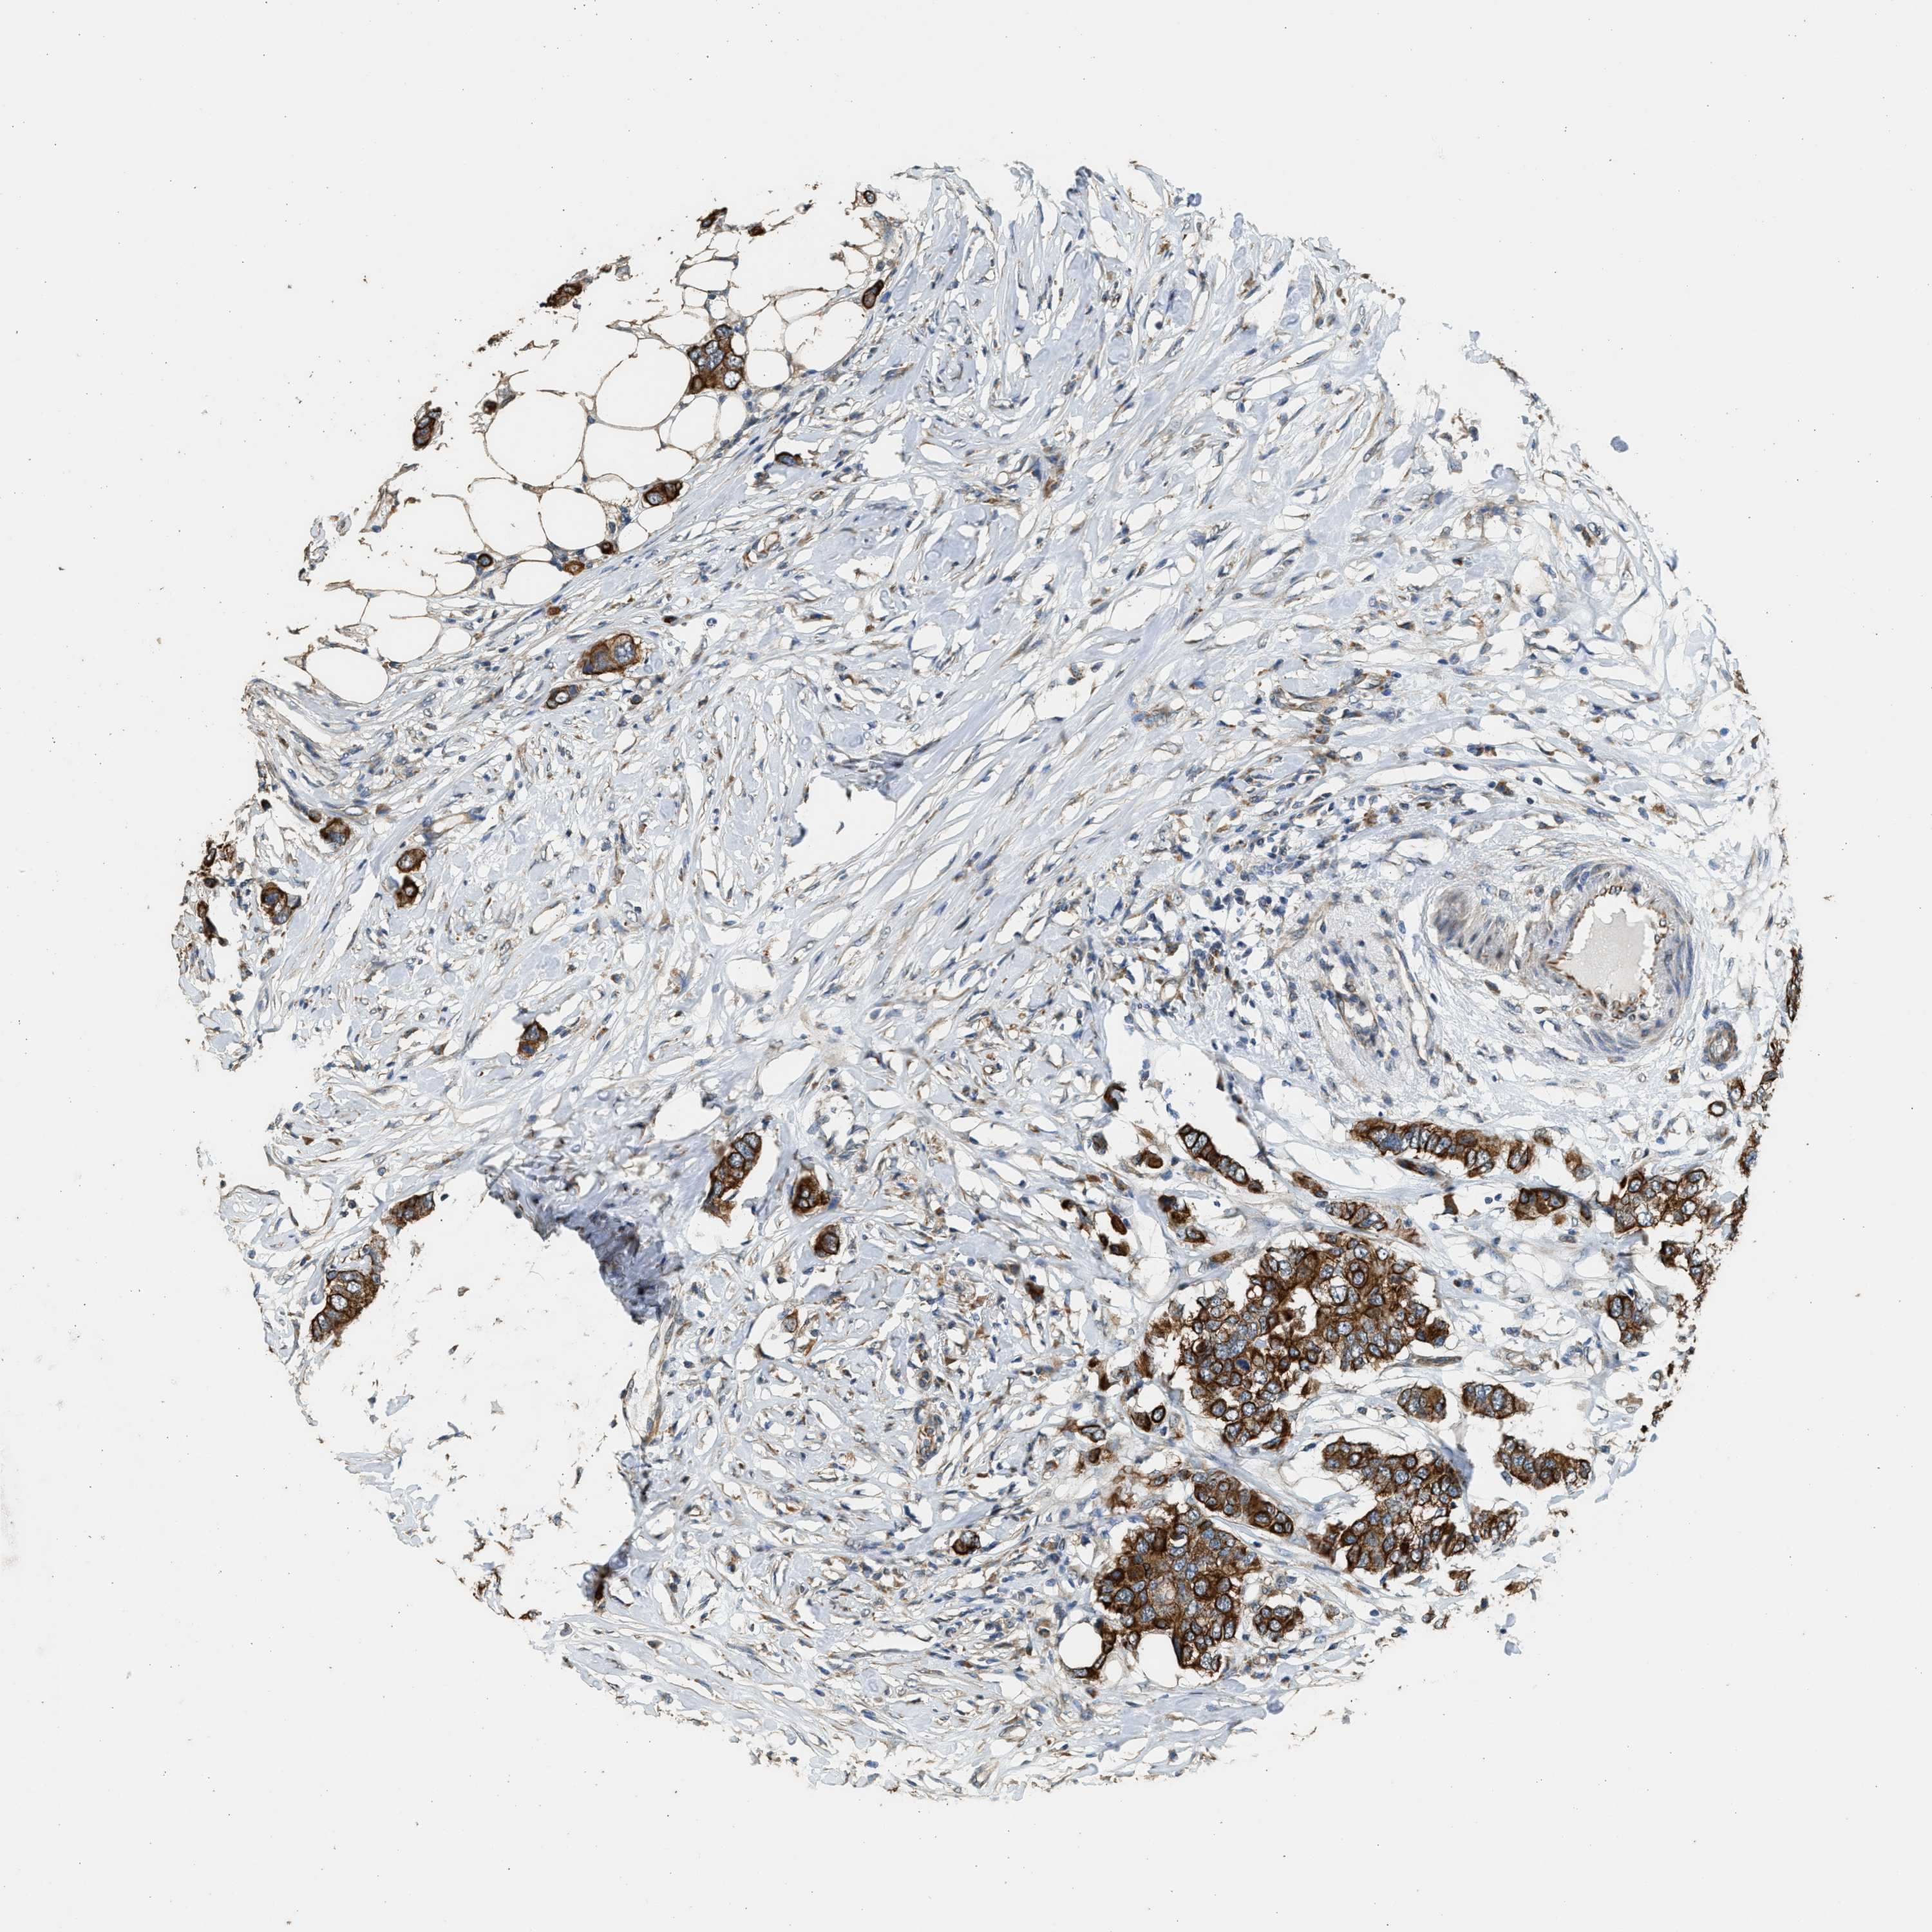

CANCER BREAST CANCER Show tissue menu

BRCA TCGA BRCA VALIDATION PROTEIN EXPRESSION

ANTIBODIES

AND

VALIDATION